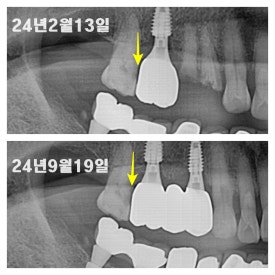

3. 충치치료 안 하시다가 결국 발치를 해야 했던 케이스

충치가 그나마 덜 진행되었을 때는 신경치료 후 크라운 치료를 통해 해결할 수 있었는데 치료를 미루다가 결국 충치가 더욱 광범위해진 상태로 오셔서 발치를 하게 되었던 케이스입니다.